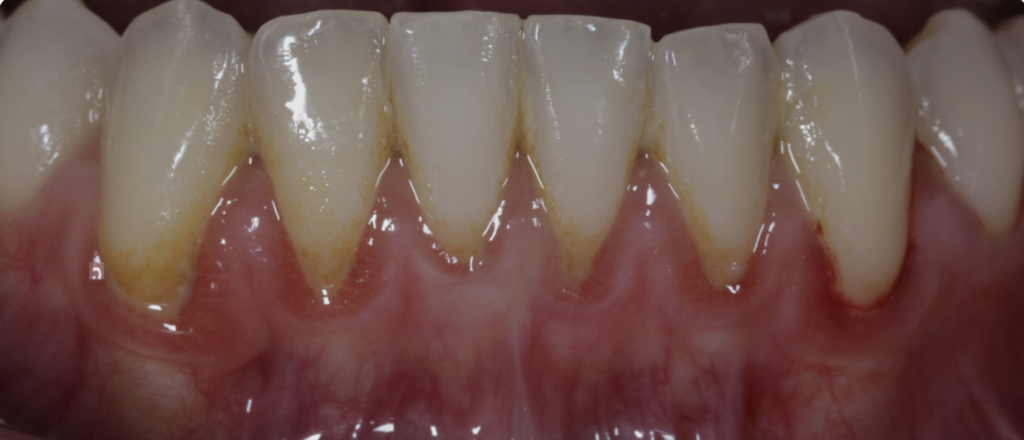

2. La enfermedad periodontal es silenciosa

La inflamación de encías suele comenzar sin dolor. Cuando aparecen síntomas evidentes, el daño puede ser significativo.

Fig. 2. Enfermedad periodontal